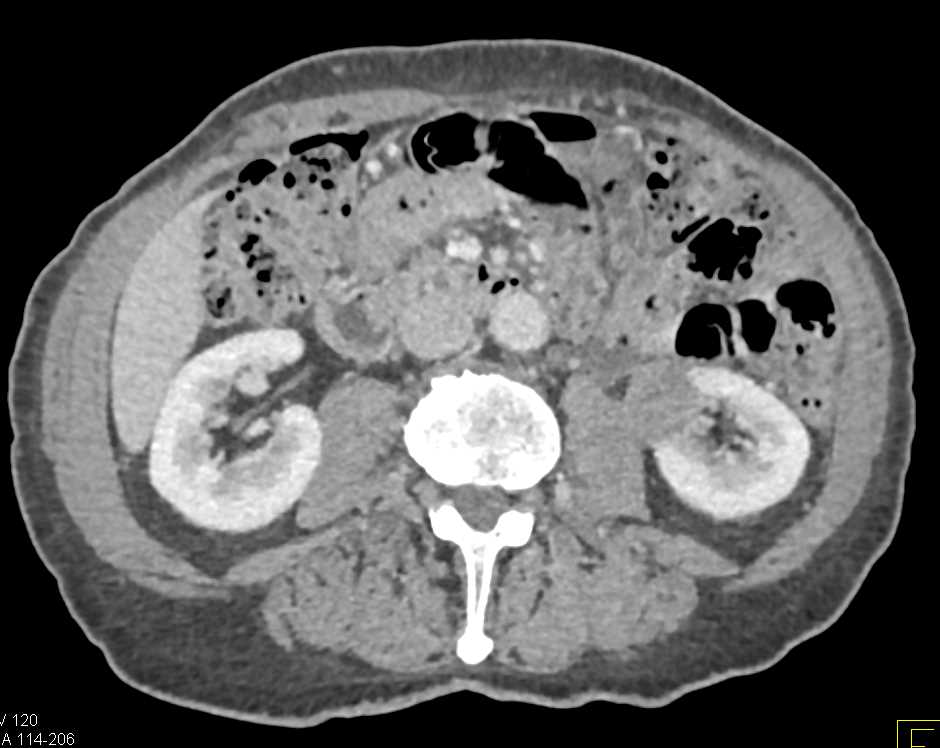

Atrophic Left Kidney